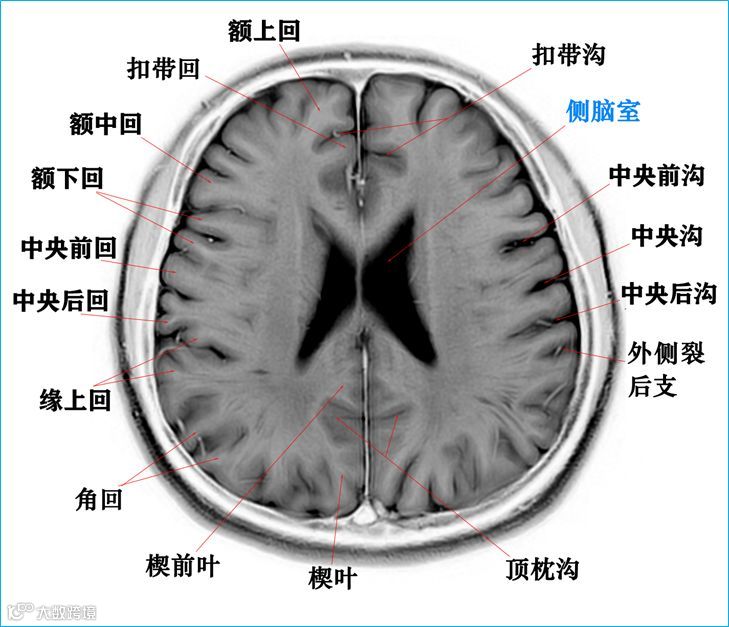

在T2WI反相图学下的颅脑断层解剖(吴晓安老师亲自手动标准)以及标本断层解剖,满满干货,坐在小板凳上,一起学习吧……